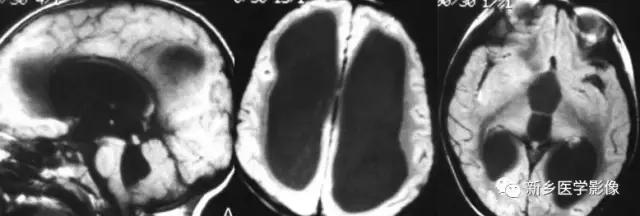

(2)脑裂畸形:胚胎期脑的发育经历6个主要阶段:①背侧诱导阶段;③腹侧诱导阶段;③神经增生阶段;④神经元移行阶段;⑤组织形成阶段;⑥髓鞘形成阶段。脑裂畸形发生在神经元移行阶段。脑裂畸形可累及一侧或双侧大脑半球,脑裂畸形位于侧面.常累及中央前、后回区偶尔位于大脑半球的其他部位。脑裂畸形的裂隙可以很窄,裂隙两侧灰质紧密相贴,称闭合型。裂隙也可以很宽,中间为脑脊液,分离型。

分离型脑裂畸形需要与脑穿通畸形囊肿鉴别.脑裂畸形的裂隙两旁一定为一灰质结构,而脑穿通畸形囊肿周围无脑灰质包绕。裂隙两旁是否为灰质结构是区别脑裂畸形与脑穿通畸形囊肿的可靠征象。裂隙两侧的灰质可不正常,可呈多小脑回样。脑裂畸形也可合并脑灰质异位。

分离型在CT很容易显示.闭合型有时容易漏诊.MRI对裂隙两侧的灰质结构容易辨认。脑裂畸形常合并透明隔缺如.侧脑室扩大,脑裂畸形处脑室边缘不规则.常可见指向裂隙的裂或 三角形憩室存在。

临床上脑裂畸形常表现有癫痫发作,其他神经系统症状可从很轻微到很严重.主要取决于脑裂畸形使脑组织缺损的严重程度。单侧闭合型脑裂畸形症状通常较轻,双侧分离型脑裂畸形症状较明显。